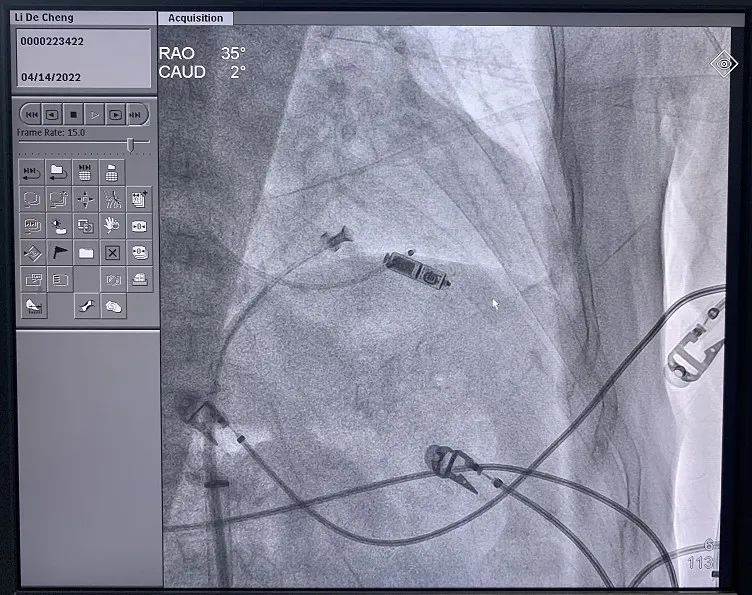

无导线起搏器术中植入影像

经过充分的术前讨论,在与家属充分沟通并知情同意下,在北京老年医院心内科王健主任团队、麻醉科程斌主任、综合介入中心黄勇军主任团队及精神心理一科张守字主任团队的共同努力下,经过多学科协作,应用国内外先进技术,在临时起搏器保驾下,全麻保障过程中,成功为这位高龄老人植入无导线起搏器,为患者的心率提供了最有效的保障。